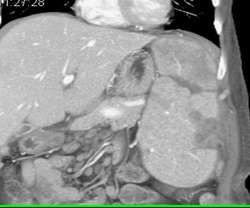

Splenic Infarcts